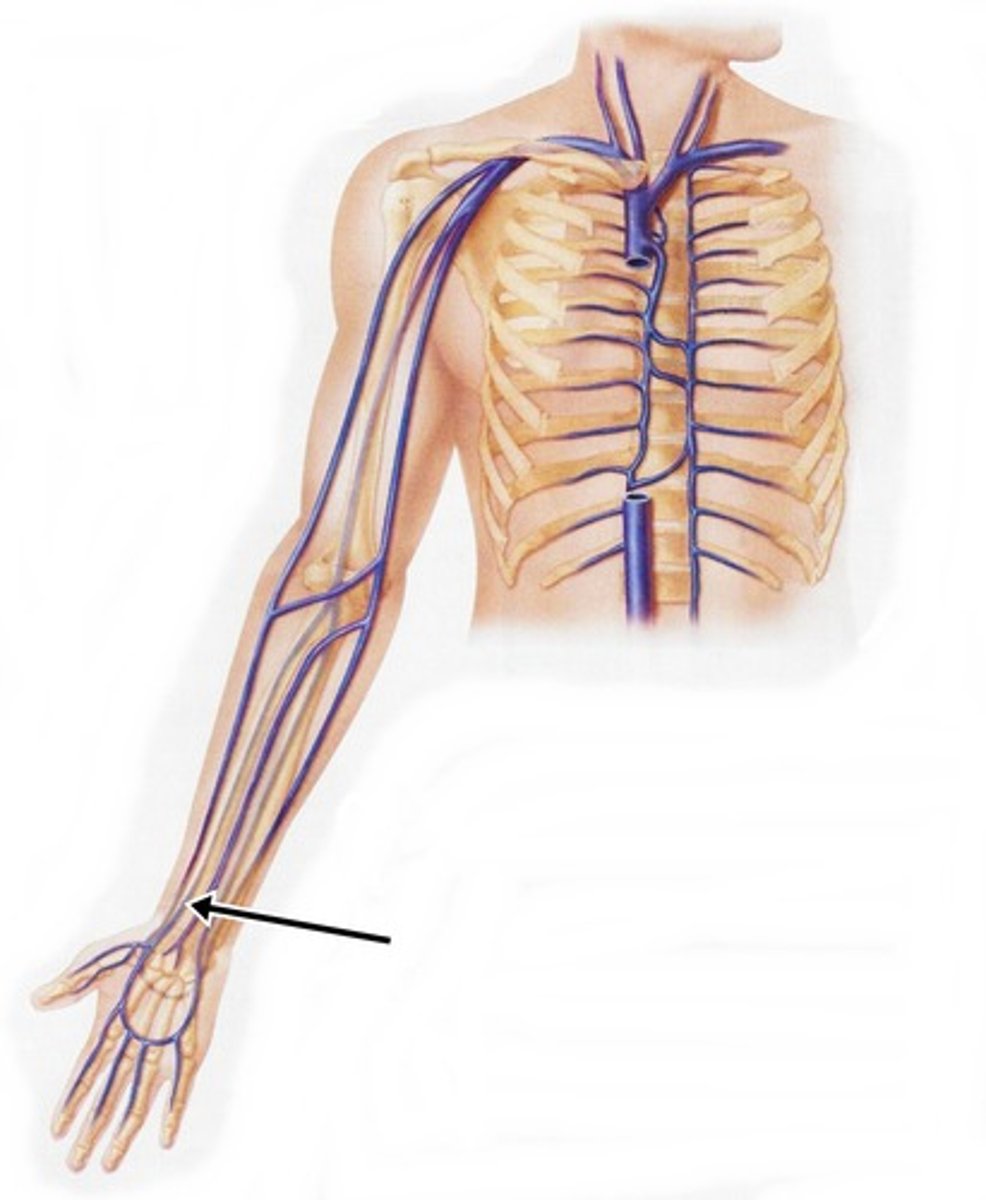

subclavian vein

superior vena cava

axillary vein

brachial vein

cephalic vein

radial vein

ulnar vein